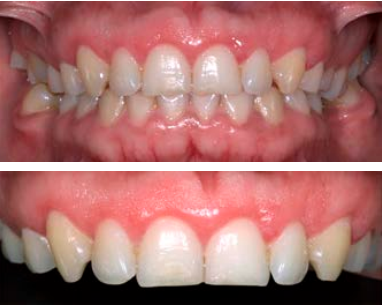

Se revisó a la paciente tras haber realizar el procedimiento quirúrgico, no presentó ninguna complicación, los tejidos gingivales con características normales, sin procesos inflamatorios y acorde con el proceso de cicatrización (Figura 5).